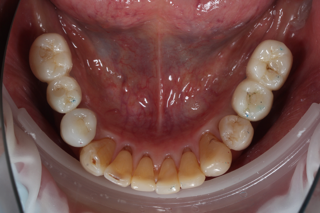

上 after

下 after